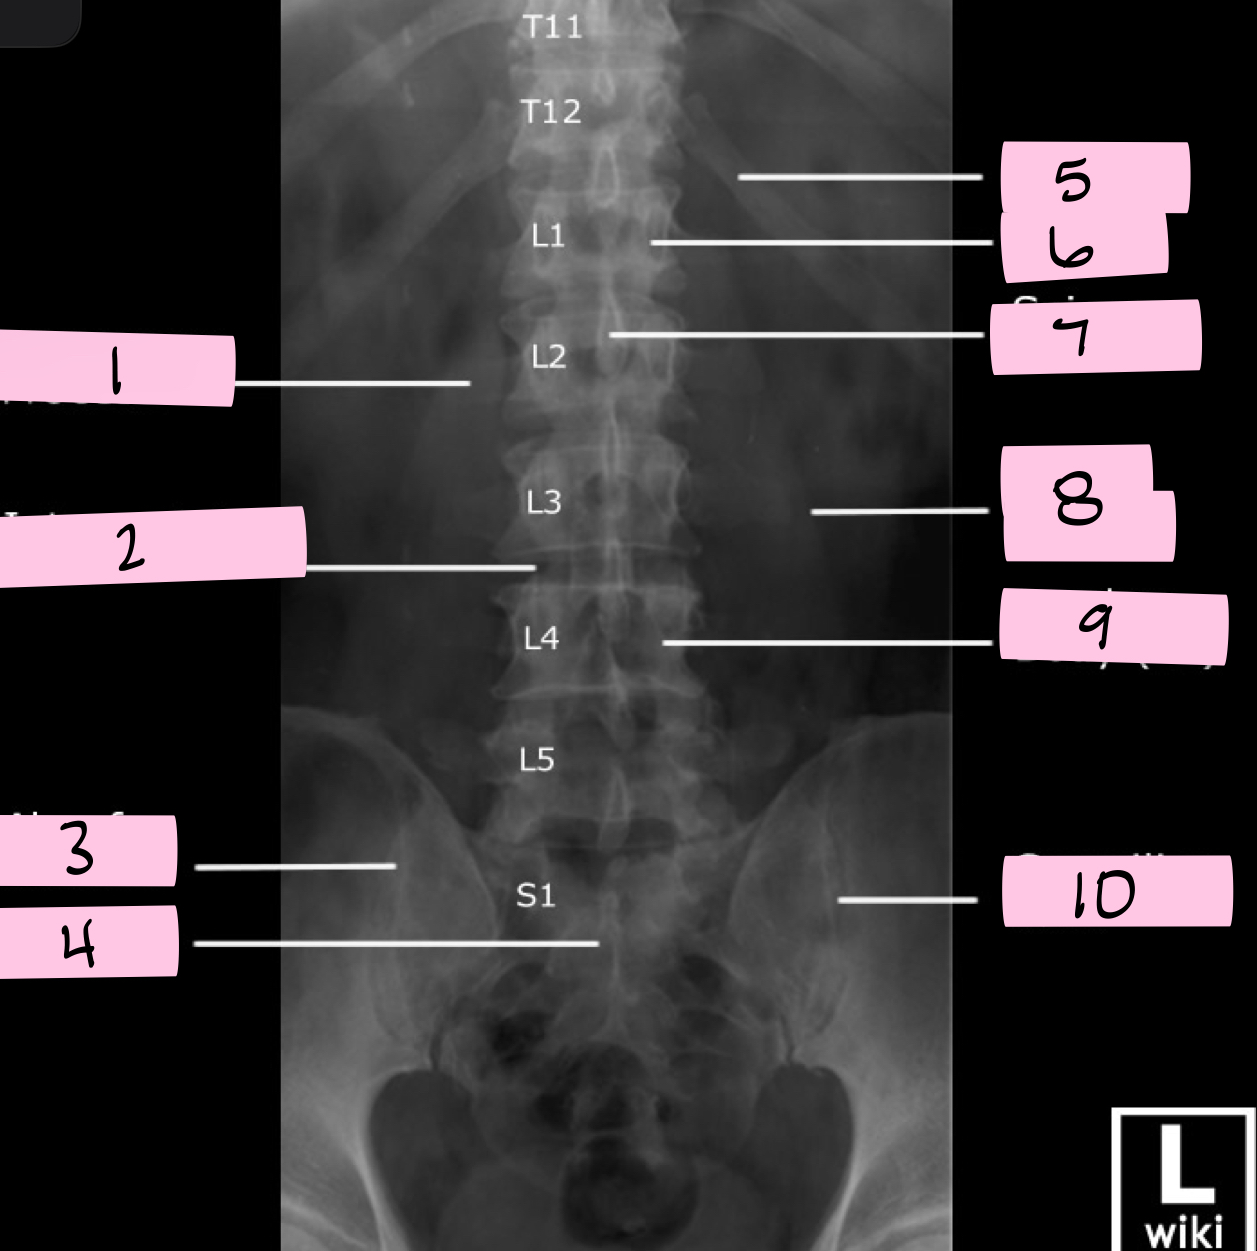

What is 1 pointing to?

Transverse process

What is 2 pointing to?

Intervertebral disk

What is 3 pointing to?

Ala of sacrum

What is 4 pointing to?

Sacrum

What is 5 pointing to?

12th Rib

What is 6 pointing to?

Pedicle

What is 7 pointing to?

Spinous process

What is 8 pointing to?

Psoas muscle

What is 9 pointing to?

Lumbar body (L4)

What is 10 pointing to?

Sacroiliac joint